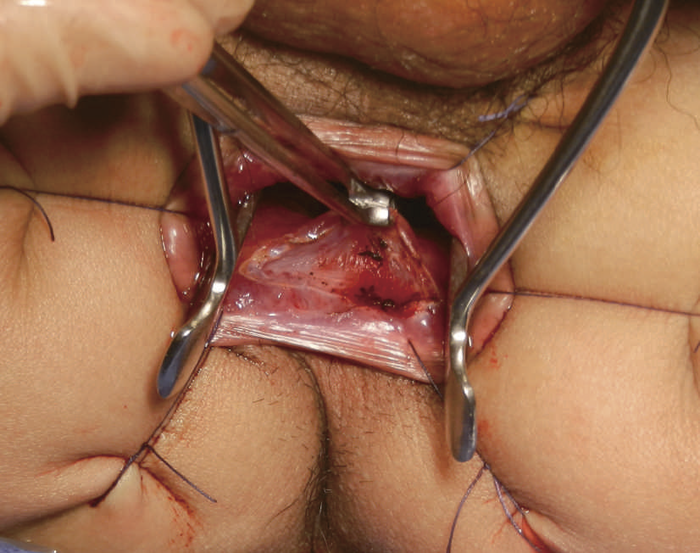

(1)大腸全摘,回腸囊肛門吻合術(Ileoanal anastomosis:IAA)

直腸粘膜をすべて切除し,回腸囊と肛門を手縫い吻合する。UCに対しても根治性が高い術式である。図14のように,肛門管粘膜の切除開始ラインは歯状線の肛門側で,肛門陰窩をすべて切除する。切除開始ラインが歯状線よりも口側になり,一部肛門管粘膜(移行帯上皮)を温存させた結果,この残存した粘膜からの発癌を強く示唆する症例報告も存在する2)。また,IAAを行ったにもかかわらず,術後に発癌したという症例報告も存在するが,多くは術後3年以内に発症している症例が多く,術前の直腸癌の局所再発が原因ではないかとの意見が一般的である3)。下部直腸から肛門管にかけて早期癌を合併するような症例では,術後の病理検査で,DM0,RM0であっても図15のように局所再発を生じる可能性もあるので,定期的な画像診断とともに,直腸診を行い,局所再発がないことを確認すべきである4)。

図14 IAA時の粘膜切除の開始ライン